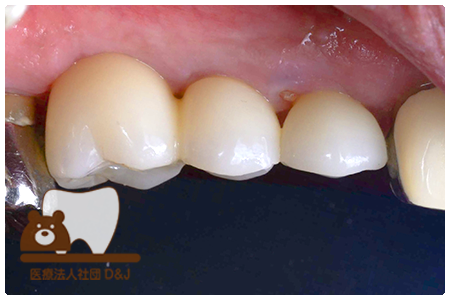

症例2フルジルコニアクラウン 左上4

治療前

治療後

63歳 男性

- 治療内容

- 根管治療の後でフルジルコニアクラウンを装着しました。

- 治療期間

- 根の治療含めて1カ月半

- 費用

- 自費

フルジルコニアクラウン:77,000円(税込)

(R8.2月時点)

- その他の治療の費用は含まれておりません。

- リスク・副作用

- 強い力が加わると割れる可能性があります。また、噛み合わせや歯ぎしりの影響で脱離することがあります。